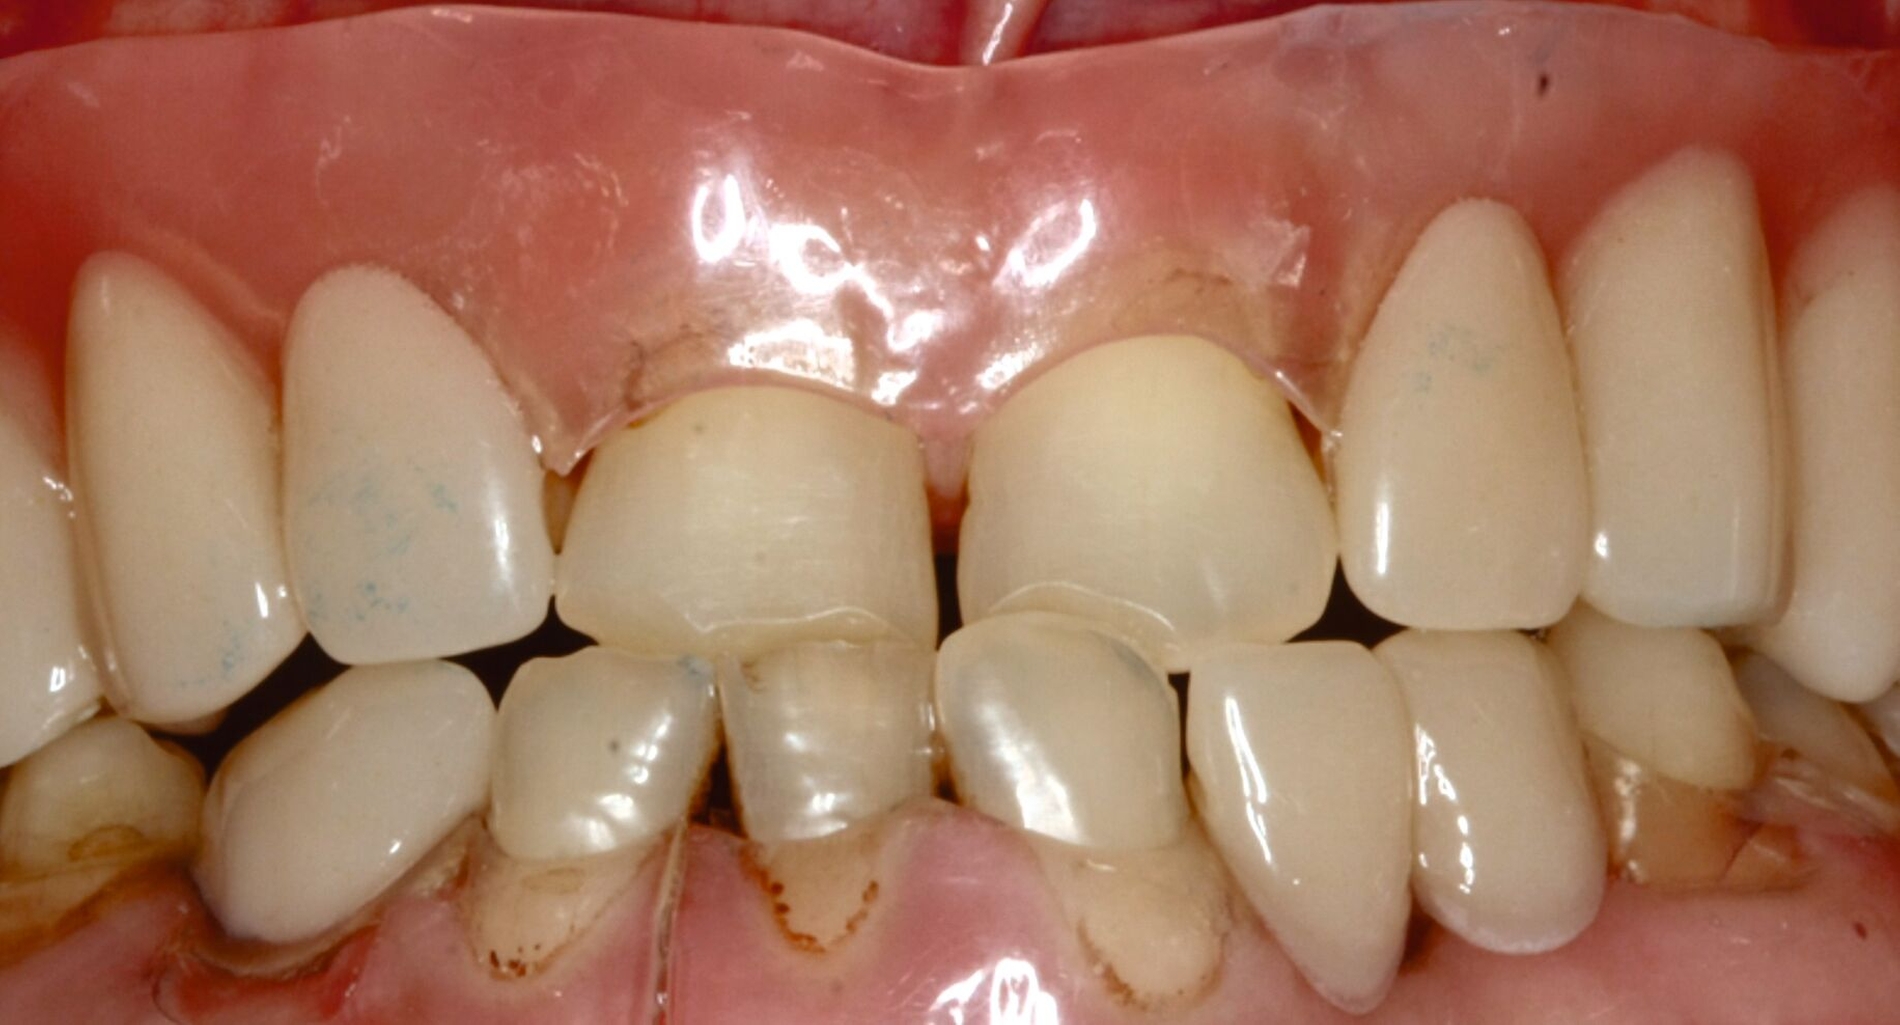

Ein 30-jähriger Patient stellte sich mit multipler Oligodontie (15 fehlende bleibende Zähne), Persistenz von Milchzähnen sowie ausgeprägter Dysgnathie mit progenem Deckbiss vor. Klinisch zeigten sich hypoplastische Restzähne, Fehlstellungen und erhebliche funktionelle Beeinträchtigungen (Abbildung 1). Sein Wunsch bestand in einer möglichst optimalen ästhetischen und funktionellen Versorgung seiner für ihn äußerst unbefriedigenden Gebisssituation. Die molekulargenetische Analyse bestätigte eine homozygote Mutation im WNT10A-Gen als Ursache der Zahnagenesie.

Eine mögliche und indizierte Umstellungsosteotomie wurde vom Patienten abgelehnt. Da seitens des Patienten eine Kopfbissstellung möglich war, wurde eine Bissumstellung und -hebung mit nur noch geringgradigem Vorbiss und anschließender Zahnimplantation in Erwägung gezogen. Begonnen wurde mit einer temporären Schienentherapie zur Neuorientierung der Bisslage (Abbildung 3). Da der Patient die angepasste Bisshebung tolerierte, wurde diese nach Entfernung der persistierenden Milchzähne 55, 53, 52, 62 und 83 temporär mittels einer Valplastprothese (Abbildung 4) als Interimsersatz im Oberkiefer gesichert.